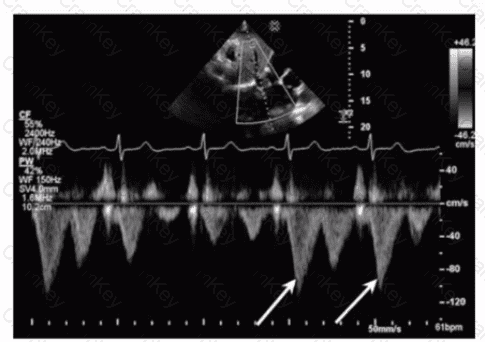

Which flow component is indicated by the arrows on this image?

The Doppler waveform shows pulmonary vein flow with several components. The arrows point to small reversed flow spikes just after the atrial contraction wave, which corresponds to the atrial reversal (AR) flow component. Atrial reversal occurs as blood briefly flows backward into the pulmonary veins during atrial contraction.

Ventricular reversal is not typically seen in pulmonary veins. Diastolic flow reversal is abnormal and usually not part of normal pulmonary vein flow. Systolic forward flow is the major forward component during ventricular systole.